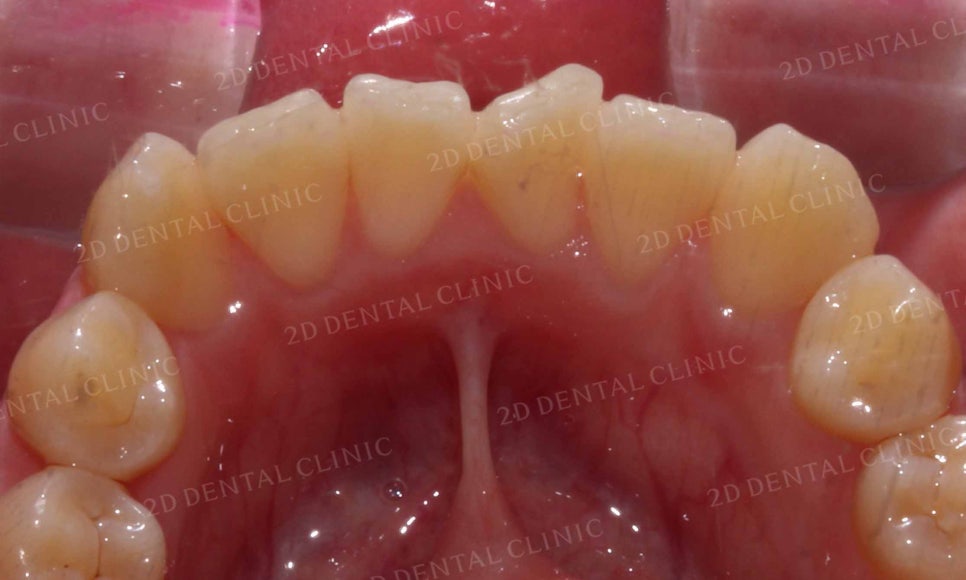

아랫니의 안쪽 면을 보시면

윗니보다 치열의 틀어짐이 심하고

삐뚤삐뚤한 모습인데요,

치아의 겉면이 아닌 안쪽면에

교정장치를 부착하는 2D교정을 통해

치아의 틀어짐(총생)을 바로잡는 계획을 세웠습니다.

삐뚤삐뚤한 치열이었던 아랫니 역시

토끼앞니 교정 후 치열의 총생이 사라지고

완만한 곡선의 형태로 교정된 모습입니다.